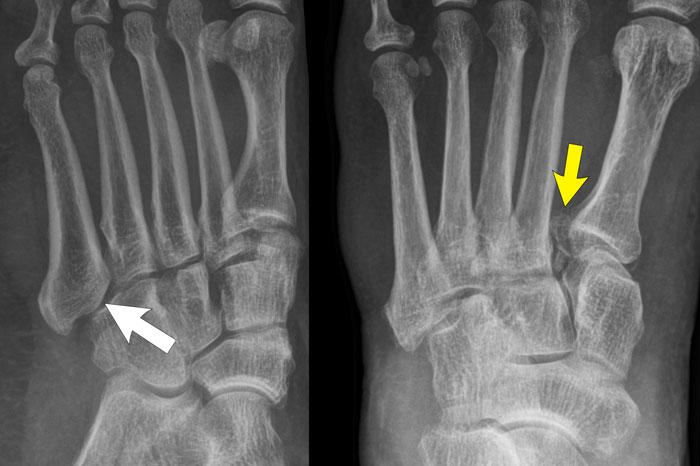

case 1 – distortion

The findings are:

- Khoảng cách lớn giữa nền xương bàn chân 1 và xương bàn chân 2 (mũi tên vàng).

- Bán trật khớp giữa xương hộp và nền xương đốt bàn chân thứ 5 (mũi tên trắng).

This means that there is a Lis Franck dislocation fracture.

CT xác nhận nhiều gãy xương ở mức độ các khớp cổ bàn chân (khớp Lisfranc).

Phức hợp dây chằng Lisfranc chạy giữa xương chêm trong (C1) và nền xương bàn chân thứ 2 và thứ 3.

It consists of 3 components:

- a dorsal ligament

- interosseous ligament

- dây chằng gan chân, có các điểm bám vào nền xương bàn chân 2 và xương bàn chân 3.

Nền của các xương đốt bàn chân tạo thành hình vòm giúp ổn định phần giữa bàn chân.

Giống như các vòm cửa sổ cổ, cần có một viên đá khóa vòm ở đỉnh để khép kín vòm lại.

Nếu viên đá này bị lấy đi, toàn bộ vòm sẽ sụp đổ.

Ở bàn chân, nền xương đốt bàn chân thứ 2 là viên đá khóa của vòm bàn chân.

Nếu nó mất kết nối với các xương đốt bàn chân khác, vòm bàn chân sẽ sụp đổ.

Điều này cũng sẽ dẫn đến nhiều vết bong gân của các dây chằng nối các nền xương đốt bàn chân với nhau.